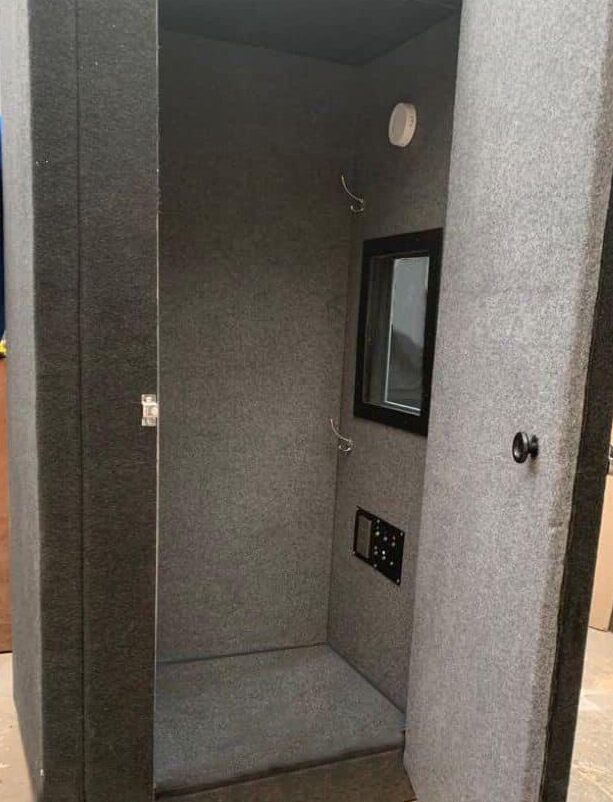

Audiometrías

El ruido de su entorno de trabajo ya no es un obstáculo para un diagnóstico preciso. Llevamos a sus instalaciones nuestra cabina sonoamortiguada móvil, donde nuestro personal certificado opera equipos de audiometría calibrados, garantizando un entorno acústicamente controlado con la misma validez y confiabilidad de un estudio de laboratorio.

Todos los estudios son interpretados por nuestro equipo de especialistas. Obtenga audiometrías de precisión clínica con comodidad móvil.

Diagnósticos Auditivos Precisos

Garantizados.

La salud auditiva de su equipo es productividad. Asegúrela con diagnósticos precisos.

Cumplimiento y prevención auditiva en la que puede confiar.

Más que una audiometría, la tranquilidad de saber que su equipo está protegido.